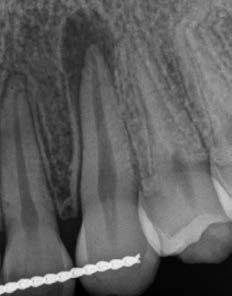

1. a-n. ábrák: Preoperatív CBCT-felvétel a bal alsó 6-os (3.6) fogról. Az axialis (a), coronalis (b) és sagittalis (c) nézeteken a mezialis és distalis gyökerek apicalis harmada körül sugáráteresztő zóna és ép buccalis corticalis csont látható. Egy olyan sablont terveztünk, amely jelezte a csontablak határait az apicalis terület pontos elérése érdekében (d). A mikrosebészeti bevatkozás során a sablont a helyére illesztettük (e), a csontablak határait megjelöltük (f) egy Piezotome CUBE LED kézi-darabba fogott fűrésszel, majd kivágtuk és eltávolítottuk (g és h) az apicalis területhez történő hozzáférés, illetve a mezialis és distalis gyökerek rezekciójának, retrográd preparációjának és retrográd gyökértömésének elvégzése érdekében (i). Végezetül a csontablakot visszaillesztettük és kollagén szivaccsal stabilizáltuk (j). A műtét után közvetlenül készített röntgenfelvétel a 3.6-os fogról (k). A kétéves kontroll során készített CBCT-felvétel: axialis (l), coronalis (m) és sagittalis (n) nézetek.

1a 1b 1c 1d

1e 1g 1h 1i 1j 1k 1f

Egy 63 éves páciens korábban már kezelt bal alsó első nagyőrlőfogából (3.6) eredő mérsékelt fájdalom miatt kereste fel rendelőnket. A kórtörténetében panasza szempontjából releváns információ nem szerepelt. Az elkészült CBCT-felvételen a korábbi kezelések során észre nem vett, jelenleg feltáratlan meziobuccalis csatornát, valamint a mezialis és distalis gyökerek körül kialakult periapicalis elváltozást, és ezt a léziót borító intakt buccalis corticalis csontlemezt láttunk.

A fog revideálását és újbóli gyökértömését két ülésben végeztük el. A régi gyökértömés eltávolítását, valamint mindhárom gyökércsatorna megmunkálását és fertőtlenítését követően kalcium-hidroxid alapú gyógyszeres zárást helyeztünk a gyökércsatornákba. A gyökértömés egy héttel később került behelyezésre. A páciens panaszai két hónap elteltével sem szűntek.

Klinikai vizsgálat során vertikális kopogtatási érzékenységet jelzett. A fog körül mérhető szondázási mélység és a fogmobilitás fiziológiás volt. A CBCT-felvételen nem észleltünk a csontos regeneráció megindulására utaló jeleket (1. a–c. ábrák). A korábban gyökérkezelt, gyökértömött és revideált 3.6-os fog esetében az alábbi diagnózis került felállításra: periodontitis periapicalis symptomatica. A panaszokat okozó fog további ellátása során navigált endodonciai mikrosebészetet kívántunk alkalmazni. Az alsó állcsontról intraorális szkent (TRIOS, 3Shape) készítettünk, és a felszíni topográfiát tartalmazó STL fájlt, valamint a CBCT-felvétel készítése során nyert DICOM fájlokat a Blue Sky Bio szoftver segítségével egyesítettük. A sebészi sablon megtervezésére az így kapott háromdimenziós képet használtuk. A sablon kialakítása során arra törekedtünk, hogy a sablon egyértelműen meghatározza a gyökércsúcsi terület eléréséhez szükséges csontablak határait (1. d. ábra)

A beavatkozás során helyi érzéstelenítésben teljes vastagságú mucoperiostealis lebenyt képeztünk, és a sablon segítségével bejelöltük a preparálandó csontablak határait. Az ablak széleinek megfelelően Piezotome CUBE LED kézi-darabbal (ACTEON) a kortikális teljes vastagságában vágást ejtettünk, majd az így kapott csontlemezt (ablakot) eltávolítottuk (1. e–h. ábra), és ezt követően steril fiziológiás sóoldatba helyeztük. A rezekció elvégzését követően (1. i. ábra) a mezialis csatornákat ultrahangos eszközök segítségével (NSK) retrográd irányból preparáltuk, majd az így kialakított mélyedésbe retrográd gyökértömést készítettünk. A tömés anyagául az EndoSequence BC RRM Fast Set Putty-t (Brasseler) választottuk. A tömés elkészítését követően a csontablakot visszaillesztettük, és a stabilizálása érdekében a vágásoknak megfelelően kialakult résekbe kollagén szivacsokat (Collagen Tape, Zimmer Biomet) helyeztünk (1. j-k. ábra). A lebenyt 6/0-s Prolene varratokkal (Corpaul) rögzítettük.

A kétéves kontroll során elvégzett klinikai és radiológiai vizsgálat (CBCT-felvétel) a periapicalis elváltozások megszűnését és a corticalis csontállomány tünet- és szövődménymentes gyógyulását

1l 1m 1n